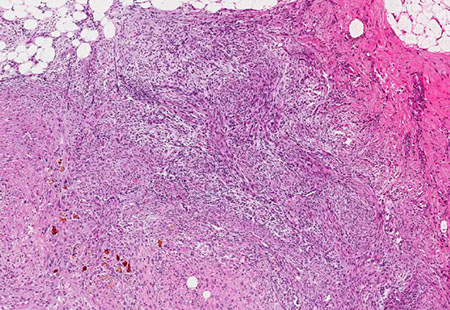

Polyarteritis Nodosa